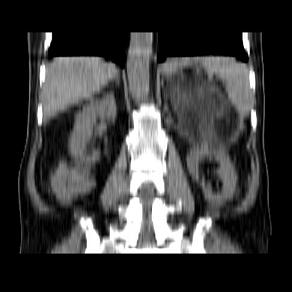

标题: CT21671:男,88岁,左上腹包块 [打印本页]

标题: CT21671:男,88岁,左上腹包块

患者因咳嗽而住院,自觉右上腹包块,无其他不适。

腹膜后高分化脂肪肉瘤

腹膜后脂肪肉瘤

腹膜生占位性病变,脂肪肉瘤可能。

脂肪肉瘤,应测ct值。

左侧腹膜后脂肪肉瘤。